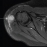

Zdrava 30-letna bolnica je pomotoma prejela cepivo proti tuberkulozi, kar je povzročilo okužbo celega telesa in s tekočino napolnjen absces v deltoidni mišici, označen s puščico.

Zdravniki so oteklino sprva pripisali vnetemu kožnemu tkivu, vendar so preiskave kasneje potrdile bakterije, ki povzročajo tuberkulozo v njenem telesu.